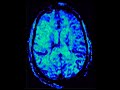

Acute Right MCA Infarct

These images show hyperattenuation of the right middle cerebral artery at the M1 and M2 segment junction on CT which is known as the hyperdense MCA sign and signifies clot.  There was no discernable loss of gray white matter differentiation on CT at this point and the patient went on to get MRI and MRA of the brain for further characterization of the extent of the acute infarct.  MRI showed restricted diffusion throughout the right MCA territory with matching perfusion abnormality and clot in the MCA as evidenced by lack of flow related enhancement on 3D time of flight imaging and blooming artifact on susceptibility weighted imaging. The patient had an old infarct involving the left periatrial white matter with hemosiderin deposition which was also noted on the CT.